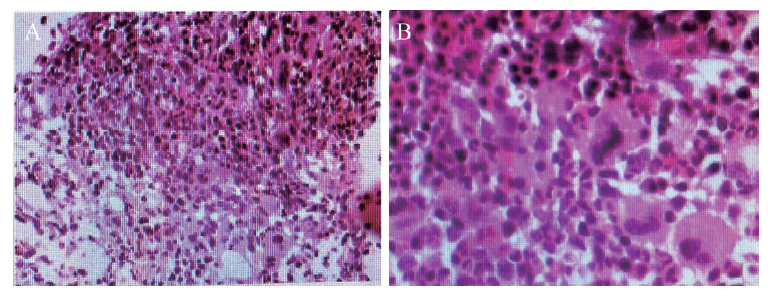

图2 一例重症AOSD患者的骨髓活检结果(HE染色)

A:×200;B:×400;图示送检骨髓穿刺组织,骨小梁间造血细胞增多,造血细胞与脂肪比例约4∶1,粒系、红系及巨核系三系造血细胞均增多,粒系可见各阶段细胞,粒细胞与红细胞比例约3∶1,巨核细胞数量未见明显异常,可见个别小巨核及单圆核细胞